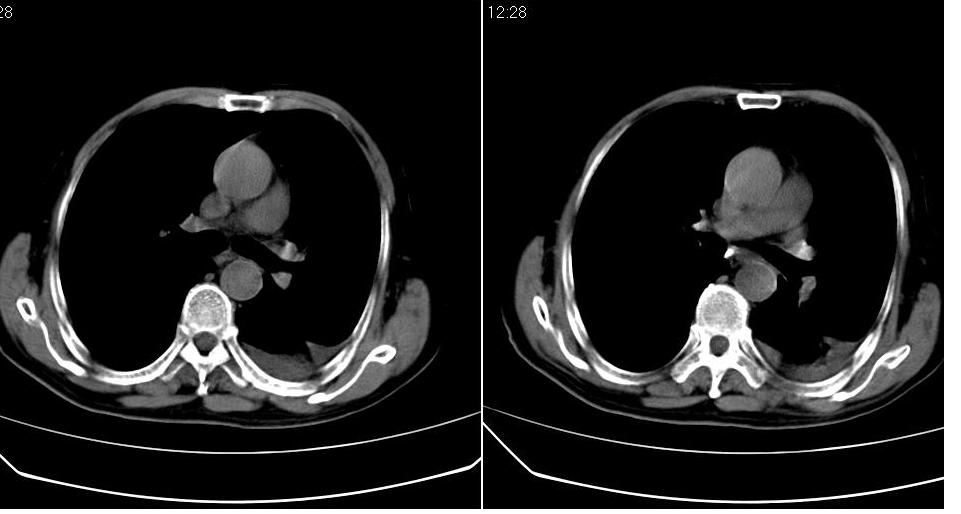

男 80岁,外院病人,有脑梗塞病史,近两个月发热,体温38.5度左右,抗炎后体温正常,药物停有发热。

左肺下叶略萎陷、实变,内可见含气支气管征。左舌叶、中叶亦见少许斑片状高密度区,边界不清。纵隔未见肿大淋巴结影。

考虑:1、肺感染;

2、建议严格抗炎治疗后复查。

左下肺体积缩小,密度增高,见片增密影。边界模糊,见支气管充气像,肺门纵隔无异示,心脏气管左移,左侧胸腔少量积液。考虑肺部感染伴部分肺不张[有脑梗塞病史坠积性肺炎可能]